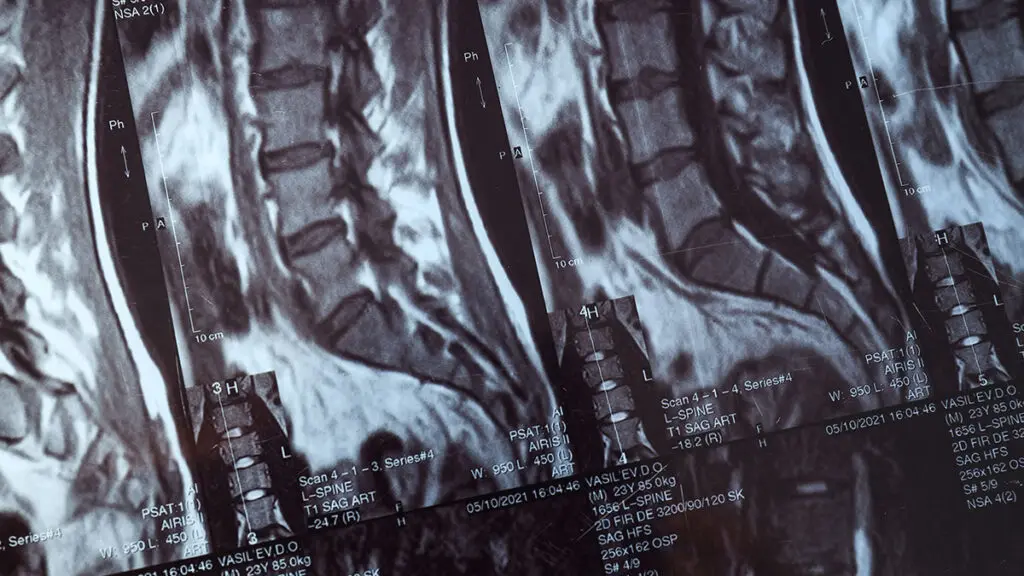

L'indicazione alla stabilizzazione vertebrale viene stabilita dopo un'accurata valutazione clinica e strumentale che include RMN, TAC e, se necessario, Rx dinamici in carico. Il piano chirurgico viene discusso con il paziente in modo trasparente, illustrando i benefici attesi, i rischi e le alternative terapeutiche disponibili.